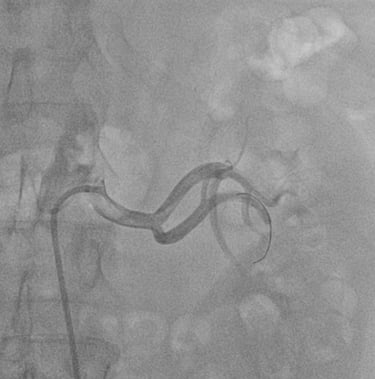

ANGIOPLASTICA

Angioplastica coronarica e lo stent

Si tratta del piu' comune trattamento attualmente utilizzato per curare l'aterosclerosi coronarica. E' una metodica che si avvale di molteplici strumenti appositamente ideati e realizzati e puo' essere effettuata subito dopo la coronarografia, utilizzando la stessa via di accesso arterioso. Solitamente, il paziente sottoposto ad angioplastica coronarica programmata puo' essere dimesso il giorno successivo alla procedura. Lo stent coronarico e' un dispositivo di grandezza millimetrica, in lega metallica biocompatibile (quindi senza fenomeni di rigetto), che viene utilizzato di solito dopo la dilatazione dell'arteria coronarica con il palloncino, per mantenere la pervietà della arteria.